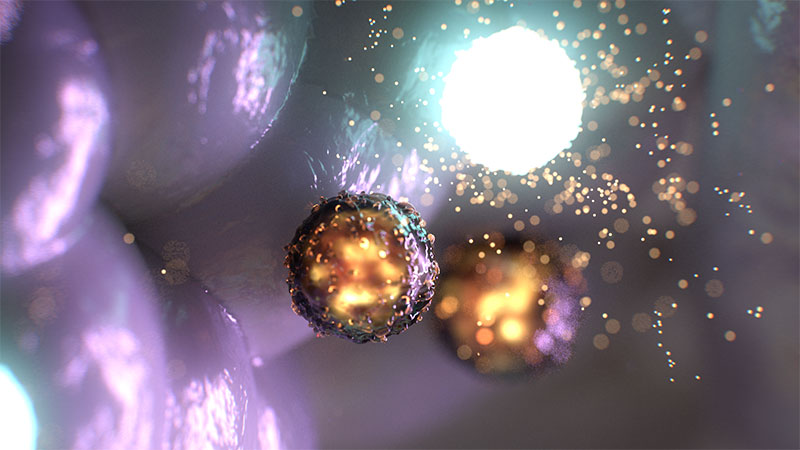

Tumor build

Tumor close-up

One of the first Microverse projects to use the workflow was an animation conveying a new therapy to treat COVID-19 that was developed by researchers at North Carolina State University and UNC-Chapel Hill. Project frames were often rendered and returned long before they were needed, avoiding down time and allowing lead animator Amanda Manowski to remain immersed in the creative process.

A lot of planning went into their approach to the overall look, the texture of the membranes, for example, and how light reacts with the membranes and other critical surfaces. The studio’s animators typically work in Maxon Cinema 4D on local workstations and render with Redshift on Conductor. Character animation techniques were used to help viewers differentiate between and identify the various particles and tissues in an animation. Amanda also had specific qualities in mind for the lighting effects and reflections.

Multiple Applications

She needed to use multiple applications to develop the geometry -- Cinema 4D X-Particles dynamics to produce and understand the general shape, and ZBrush to build out the detail. The Redshift renderer influenced every 3D scene, of course, and as well as the base materials and lighting, she built certain effects and AOV outputs through its material nodes, such as the flashing effects needed for one scene. Red Giant tools were used to add glows, and compositing was done in After Effects.